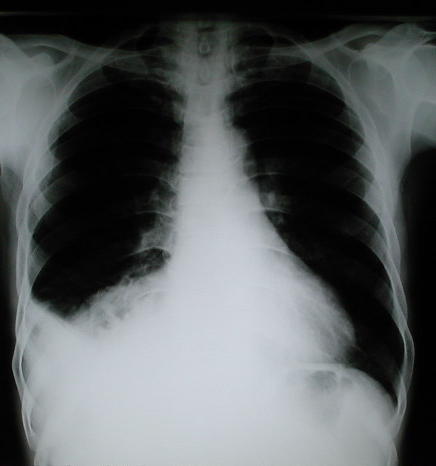

Radiología Posteroanterior del tórax

• Una radiografía torácica anormal, en octubre del 1999, reportada inicialmente como reacción pleural de tipo residual, en evaluación traumatológica por disfunción de la articulación del tobillo izquierdo sugiere evaluación neumonológica, los nuevos estudios radiológicos del tórax demuestran patología caracterizada radiopacidad basal derecha con borramiento del hemi diafragma e imágenes de aspecto hidroaereo que plantea la posibilidad de una hernia diafragmática de contenido gastrointestinal de probable etiología pos traumática.

• Puede observarse en los estudios, la hiperplasia funcional compensatoria del pulmón Izquierdo

Rx Torax Posteroanterior reciente Estudio Radiológico del torax actual, pre operatorio

También puede observarse la hiperplasia compensatoria del pulmón Izquierdo.